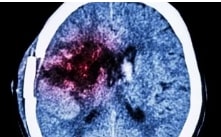

SLU research finds link between anxiety disorders, benzodiazepine exposure and dementia in seniors

Research from Saint Louis University School of Medicine finds that among patients 65 and older, a diagnosis of anxiety was significantly associated with an increased risk of dementia diagnosis, and benzodiazepine exposure was associated with a 28% increased risk of dementia. However, when benzodiazepines were prescribed to patients with an anxiety disorder, there was no significant association between these medications and incident dementia.